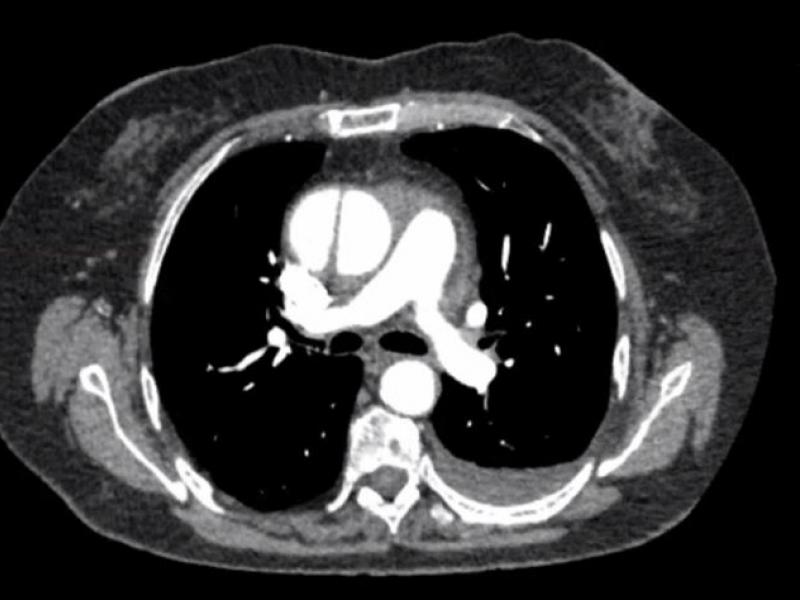

A 75 yo F w/ a history of HTN, smoking presents to the ED w/

A 45 yo male presents after syncope in rehabilitaion center